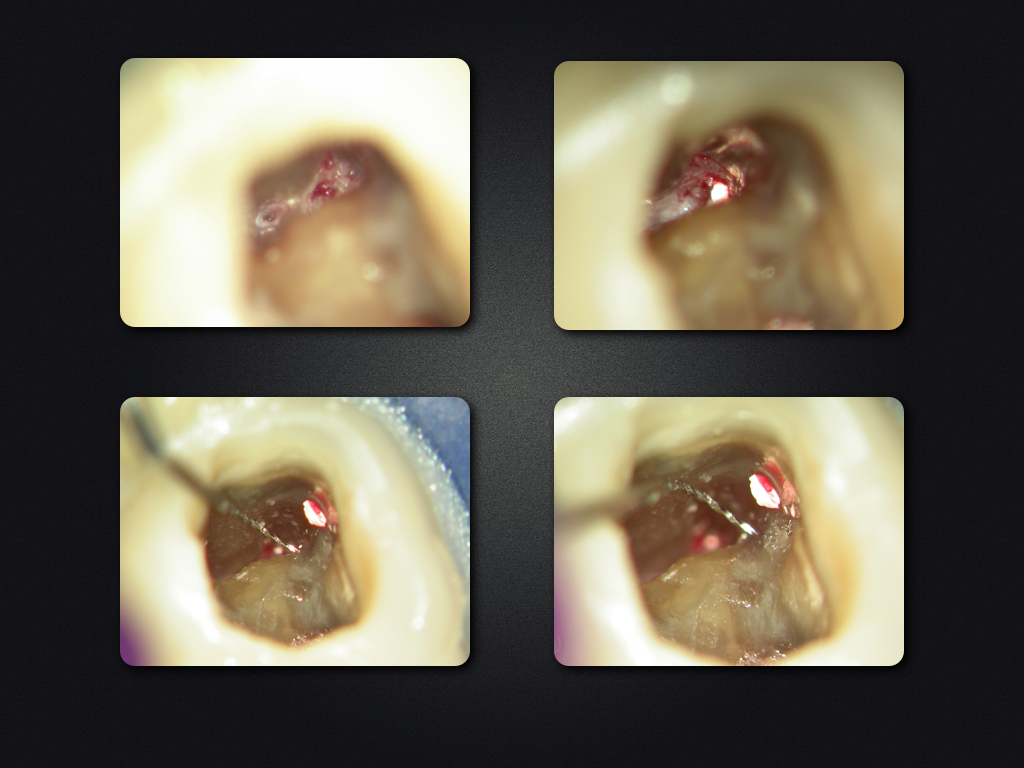

Saving Hopeless Teeth (XXXII)